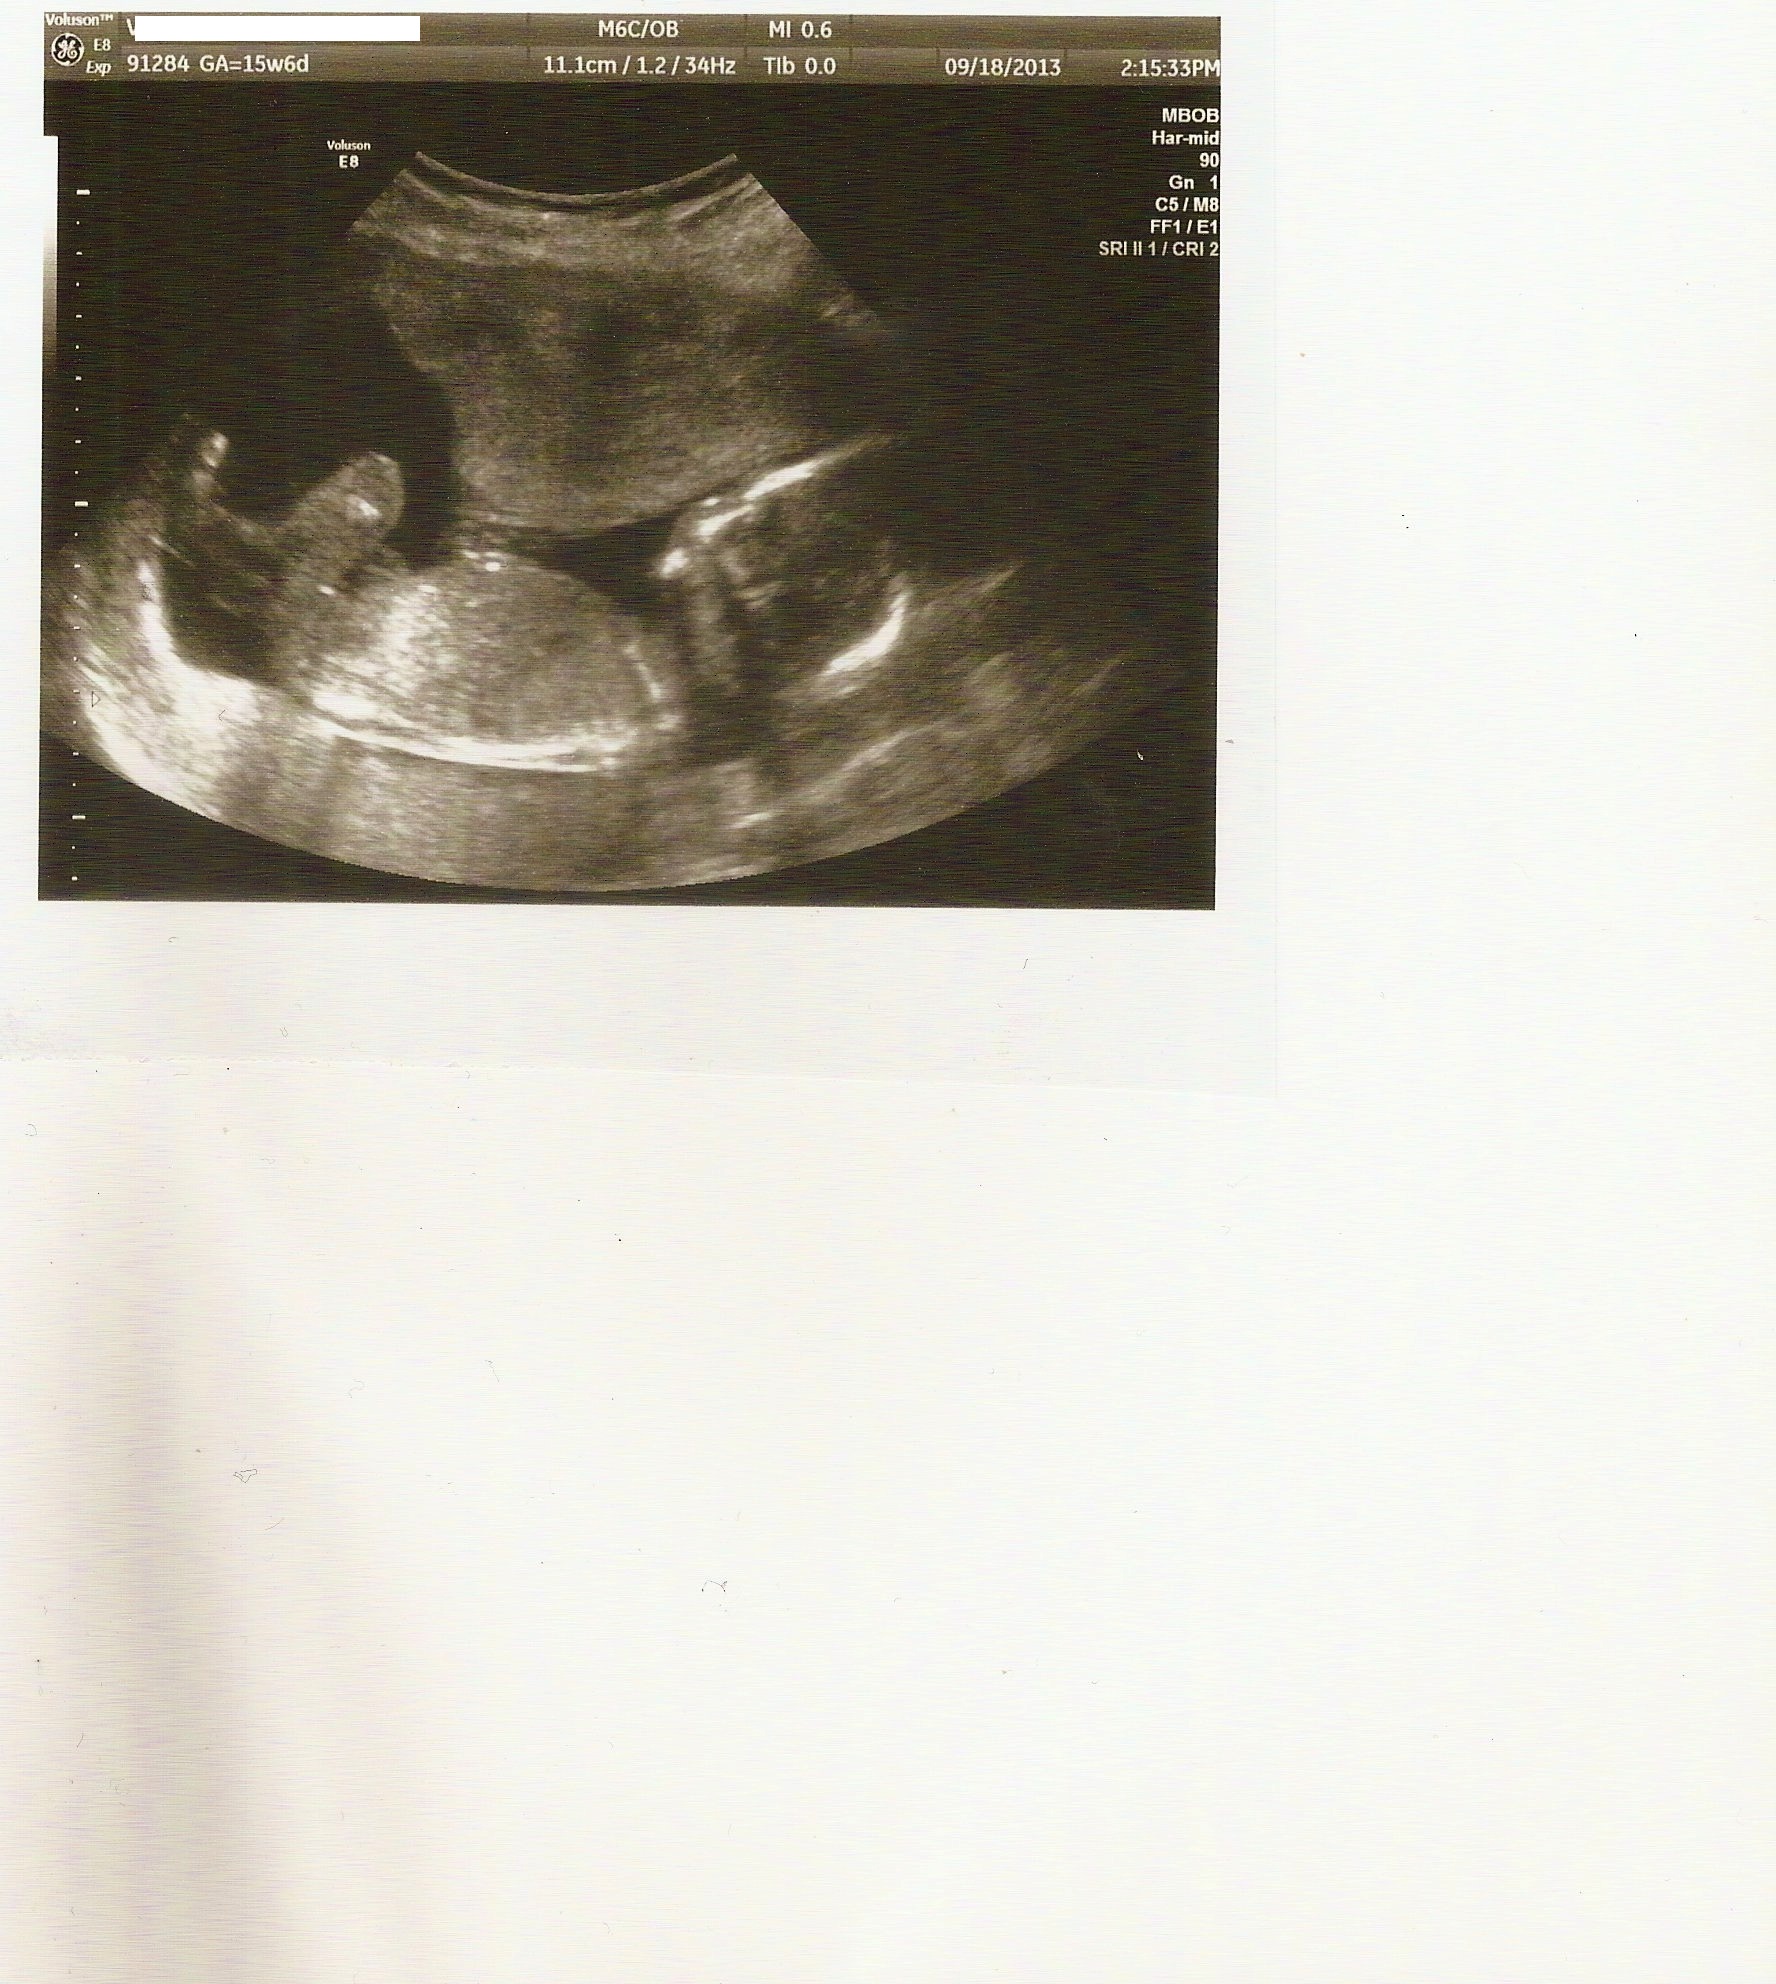

Profilovka z UT - je to holka nebo kluk?

Holky, mám jen tuto profilovou fotku z 20tt UTZ. Přijde Vám to jako holčička, nebo chlapeček? Prý podle tvaru lepky se dá předpovědět, co by to asi mohlo být.. Já nevím..Díky